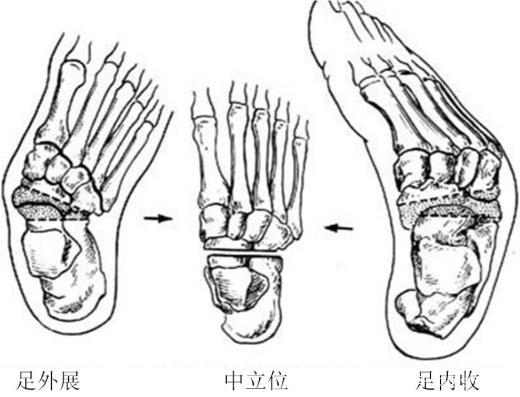

先天性马蹄内翻足的主要表现为内翻,尖足,内收和高弓,同时合并肌肉、肌腱、韧带的挛缩[2]。若不对马蹄内翻足畸形进行干预和治疗,则患者会发展成为用脚背外侧走路的步态,伴随着距下关节和跗骨关节活动度受限。

- 足内翻畸形

足内翻的影像学表现